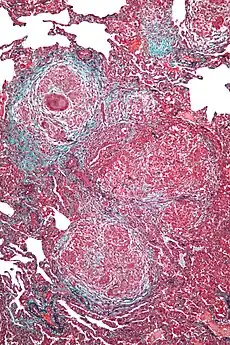

The findings are consistent with hypersensitivity pneumonitis with poor drainage of a large amount of granulomas -

High magnification micrograph of hypersensitivity pneumonitis showing granulomatous inflammation. Trichrome stain.

Histopathology

The acute form can be characterized by poorly formed noncaseating interstitial granulomas and mononuclear cell infiltration in a peribronchial distribution with prominent giant cells.[9] The subacute, or intermittent, form produces more well-formed noncaseating granulomas, bronchiolitis with or without organizing pneumonia, and interstitial fibrosis.[9] Much like the pathogenesis of idiopathic pulmonary fibrosis (IPF), chronic HP is related to increased expression of Fas antigen and Fas ligand, leading to increased epithelial apoptosis activation in the alveoli.[23] Cholesterol clefts or asteroid bodies are present within or outside granulomas.[9]